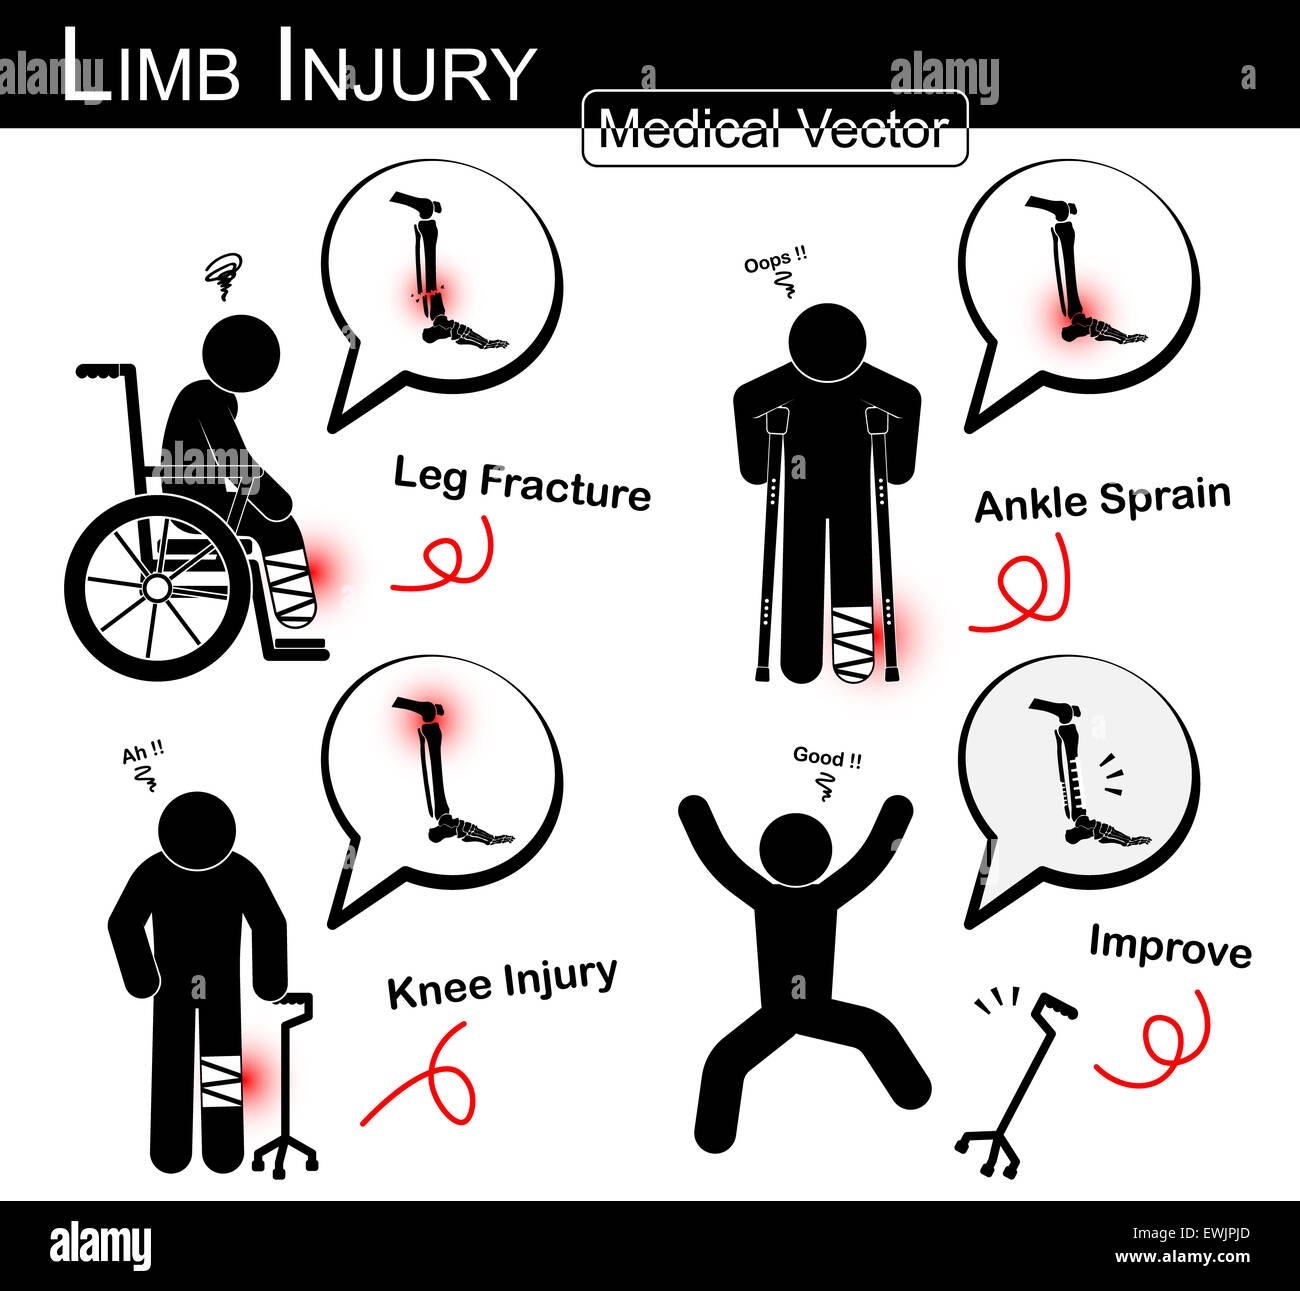

Série de blessures des membres supérieurs ( stick man avec béquille axillaire , fauteuil , canne trépied ) ( Fracture du tibia et du péroné , l'entorse de la cheville au genou , arthralgies )( vect Illustration de Vecteurhttps://www.alamyimages.fr/image-license-details/?v=1https://www.alamyimages.fr/photo-image-serie-de-blessures-des-membres-superieurs-stick-man-avec-bequille-axillaire-fauteuil-canne-trepied-fracture-du-tibia-et-du-perone-l-entorse-de-la-cheville-au-genou-arthralgies-vect-133723022.html

Série de blessures des membres supérieurs ( stick man avec béquille axillaire , fauteuil , canne trépied ) ( Fracture du tibia et du péroné , l'entorse de la cheville au genou , arthralgies )( vect Illustration de Vecteurhttps://www.alamyimages.fr/image-license-details/?v=1https://www.alamyimages.fr/photo-image-serie-de-blessures-des-membres-superieurs-stick-man-avec-bequille-axillaire-fauteuil-canne-trepied-fracture-du-tibia-et-du-perone-l-entorse-de-la-cheville-au-genou-arthralgies-vect-133723022.htmlRFHNFH26–Série de blessures des membres supérieurs ( stick man avec béquille axillaire , fauteuil , canne trépied ) ( Fracture du tibia et du péroné , l'entorse de la cheville au genou , arthralgies )( vect

Série de blessures des membres supérieurs ( stick man avec béquille axillaire , fauteuil , canne trépied ) ( Fracture du tibia et du péroné , k , entorse de cheville Banque D'Imageshttps://www.alamyimages.fr/image-license-details/?v=1https://www.alamyimages.fr/photo-image-serie-de-blessures-des-membres-superieurs-stick-man-avec-bequille-axillaire-fauteuil-canne-trepied-fracture-du-tibia-et-du-perone-k-entorse-de-cheville-84620773.html

Série de blessures des membres supérieurs ( stick man avec béquille axillaire , fauteuil , canne trépied ) ( Fracture du tibia et du péroné , k , entorse de cheville Banque D'Imageshttps://www.alamyimages.fr/image-license-details/?v=1https://www.alamyimages.fr/photo-image-serie-de-blessures-des-membres-superieurs-stick-man-avec-bequille-axillaire-fauteuil-canne-trepied-fracture-du-tibia-et-du-perone-k-entorse-de-cheville-84620773.htmlRMEWJPJD–Série de blessures des membres supérieurs ( stick man avec béquille axillaire , fauteuil , canne trépied ) ( Fracture du tibia et du péroné , k , entorse de cheville